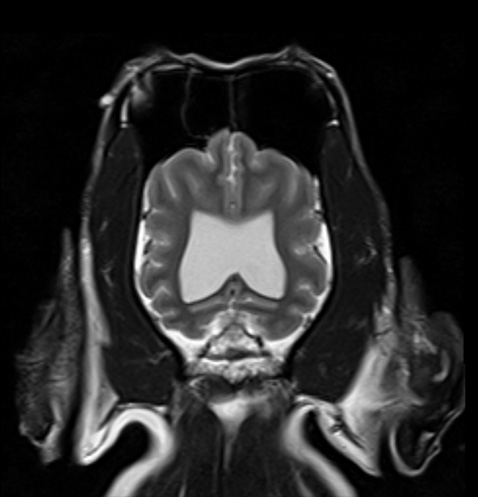

MRI는 자기장 내에서 신체에 고주파를 전사해 반향되는 전자기파를 측정 및 재구성하여 영상을 얻어 질병을 진단하는 검사로, 일반 방사선 검사(x-ray), 전단화 단층 촬영(CT)과 비교하여 방사선 피폭이 없고, 영상 대조도 및 해상도가 연부 조직과 뇌 검사에 뛰어난 장점을 가집니다. MRI는 뇌수두증이나 뇌종양 등 두개내 질환, 디스크탈출, 척수 질환 및 관절염과 인대 파열 등의 관절 질환의 평가에 유용하며 병변의 정확한 진단에 도움을 주고, 이를 통해 이후 빠른 내∙외과적인 치료를 가능하게 합니다.